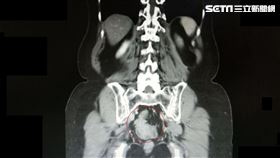

妙齡女常喊肚子痛 竟腫瘤塞腸癌末!

一名28歲的宋小姐長年在日本工作,無特殊病史且生活作...